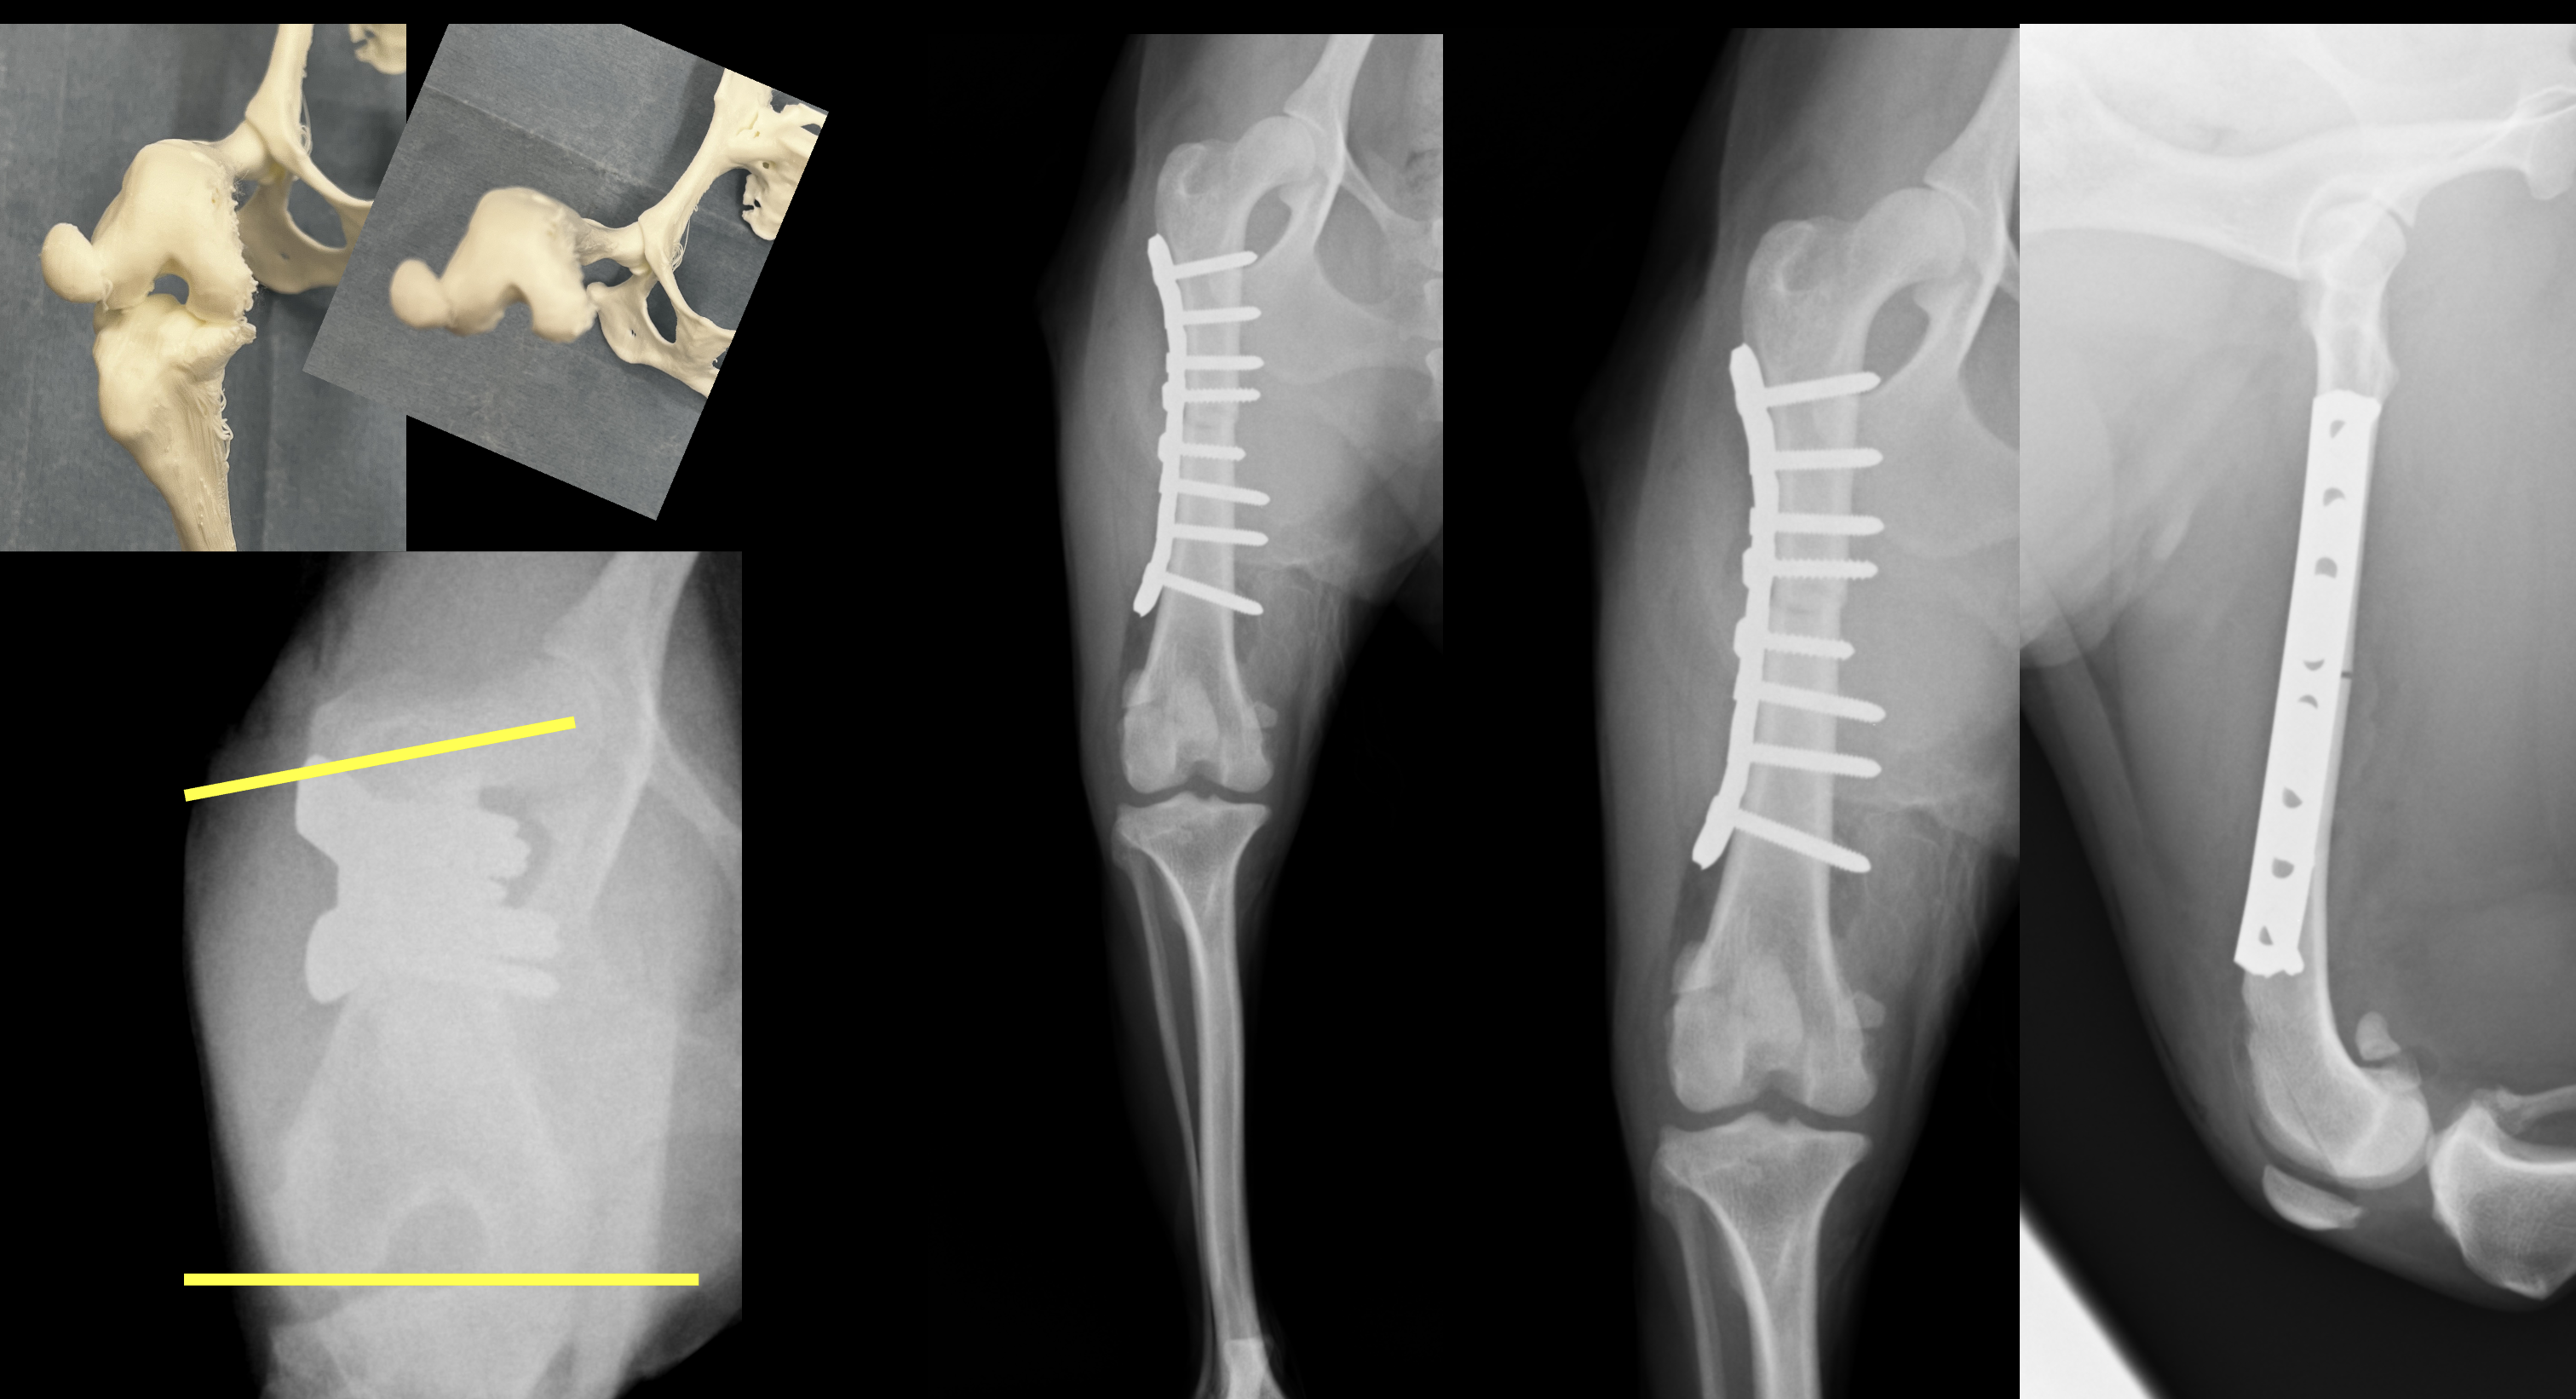

膝蓋骨外方脱臼(LPL)は小型犬では少なく、全体の10%以下と言われています。また、犬のLPLの治療は特に大型犬では成功率は非常に低いという報告があります。一方で、小型犬でのLPLの治療に滑車溝形成術、脛骨粗面転移術、軟部組織の手術を行なったところ、治癒率は高かったという報告もあります。現在のところ、小型犬膝蓋骨外方脱臼に対する報告は少なく、その治療方法は個々の獣医師の裁量に委ねられているところがあります。今回、小型犬の両側膝蓋骨外方脱臼(LPL)に対して、大腿骨前捻角矯正を行なったところ、治療が奏功した1例を紹介します。 症例はスピッツ、避妊雌、5歳1ヶ月齢、6.8kgです。既往歴は保護犬のため不明です。両後肢ともに曲がってしまっており、歩き方がおかしく、段差を降りることができないという主訴で来院されました。